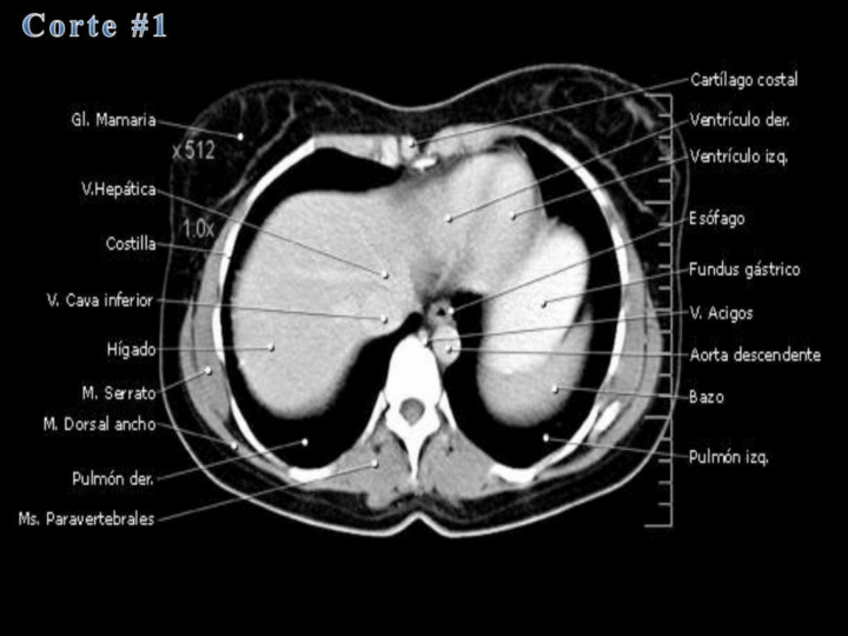

He publicado nuevos apuntes de Anatomía por la imagen: Imagenes-TC-RM-abdominal.pdf

63 páginas